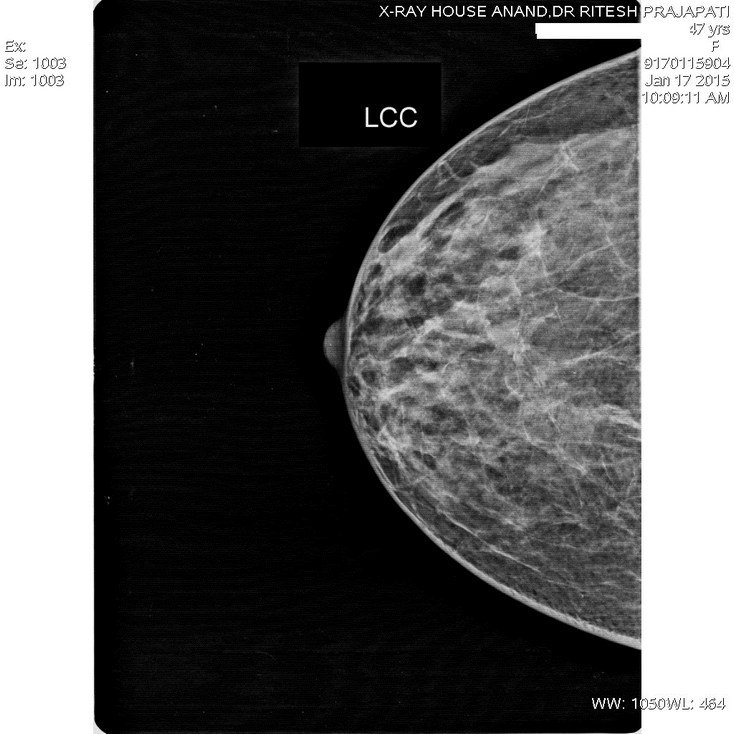

Mammograpgy-Normal

Mammography -Normal